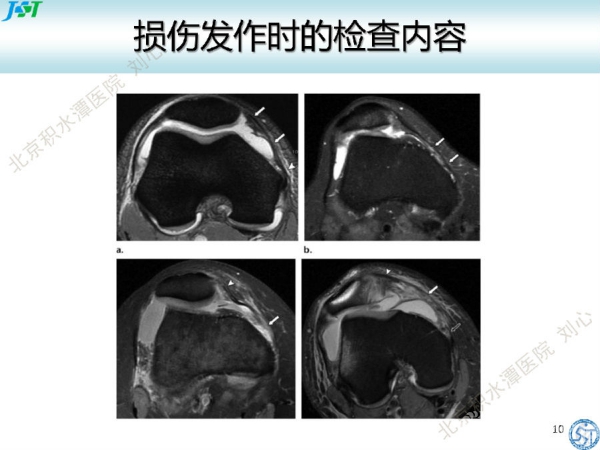

编者按:“一百个读者就有一百个哈姆雷特”,同一张片子,临床医生和影像医生往往会因为专业背景和关注焦点不同而读出不一样的结论。本文由北京积水潭医院运动医学科医师刘心站在临床医生的角度畅谈“髌股关节不稳定影像学评估”。